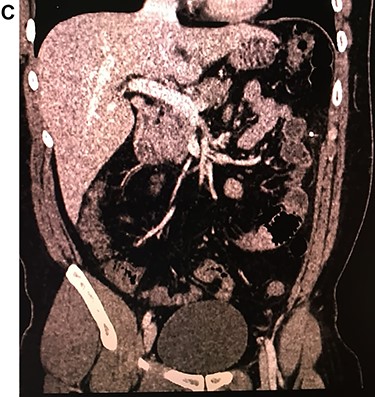

Leukocytosis with neutrophilia was detected, along with an elevated C-reactive protein. On the CT, a high-density object was seen in the descending colon; the object resembled a 4.5 cm needle that perforated the whole extent of the colonic wall. Surrounding this area there was inflammation with mesenteric edema. No lymph nodes or other masses were detected (Fig. 1A, 1B, 1C).